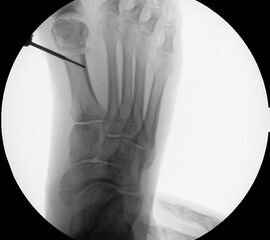

• Korrekturpotential größer als beim offenen Chevron, da die Gelenkkapsel als stabilisierendes Element erhalten bleibt und über eine trikortikale Osteosynthese mit zwei kanülierten Schrauben eine Verschiebung bis ca. 80% des Metatarsaledurchmessers möglich ist (Abb. 1).